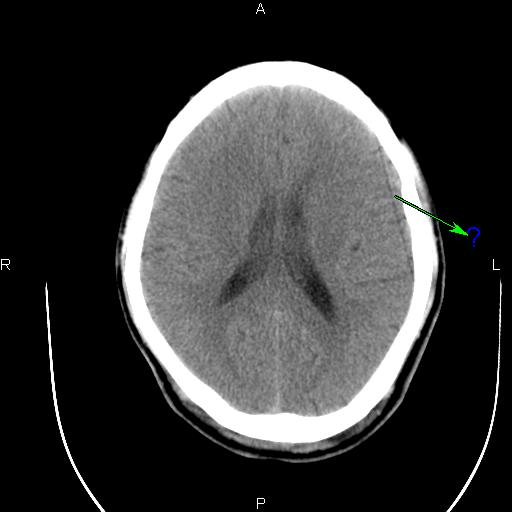

这种伪影是怎样造成的?怎样解决呢?

应该是某个通道跳起引起的直线伪影。你可以在过滤成像里检查一下,应该可以看到一跟亮线,找到是某个通道,然后屏蔽就可以了。另外一种方法就是,在ps里,不放线,不旋转,之间看所有的通道值,有没有跳起的?在ps里,放线,不旋转,这样可以看得更加清晰!你可以找到跳起的通道,或你也可以找到相应位置的das板,然后把有问题的das板换到边上,这样也可以解决问题。应该是检测器中间部位的某个das板或是通道引起的伪影

关于这种伪影还有一种可能是码盘是否干净的。

滑环接触不良,擦滑环应该能解决问题.